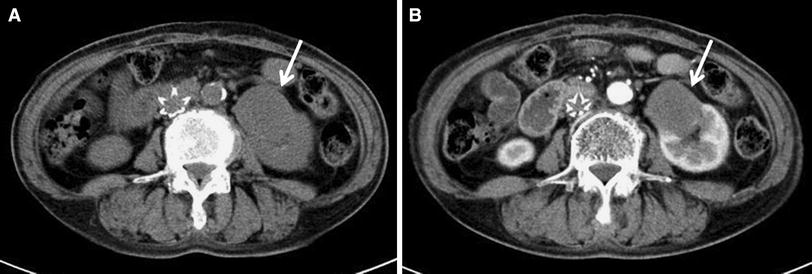

Abdominal computed tomography revealed a hypovascular tumor (4.3 × 3.5 × 4.6 cm) (arrow) in the lower pole of the left kidney (a plain, b enhanced)